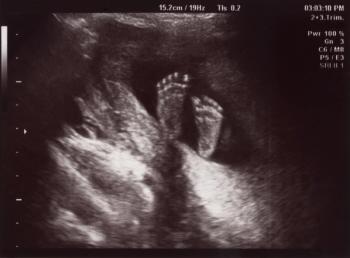

Cervical cancer survivor Ginny Marable heard about a story of a fellow cervical cancer survivor, Tamika Felder, not being able to preserve her fertility. The story moved Marable so much that she and her husband donated their embryos to Felder.

I was told that I would miscarry my pregnancy, but continued to feel more pregnant, leading to my molar pregnancy diagnosis — a condition I’ve never heard of before.